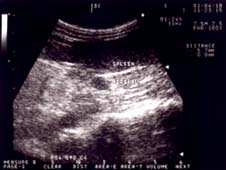

副腎疾患は、副腎より性ホルモンが過剰に分泌されることにより、色々な症状が発原します。副腎腫瘍(癌の一種)の症状は、老齢のフェレットによく見られ、極度の脱毛、虚弱、頻繁な排尿、性器からの分泌物(メス)、外陰部の肥大(メス)などがあります。血液検査で副腎の異常を推測でき、エコー検査で確認発見できます。早期に手術で腫瘍のある副腎を切除することです(ほとんど左側の副腎に腫瘍を形成することが多い)。早期治療により完治する病気ですが、数年後にもうひとつの副腎に転移することもありえます。左側の副腎は容易に摘出できますが、右側の副腎は大動脈に密着しているため高度な手術となってしまいます。副腎腫瘍の症状としての脱毛は尻尾からおこることがほとんどですが、頭から脱毛したり全然脱毛しない例もあります。

エコー検査により副腎腫瘍が発見

メスの場合、不妊手術不完全によるエストラス症と誤解されやすいので、よく検査してもらう必要があります。2才以上のメスに初めて症状があらわれた場合は手術不完全ではなく、副腎腫瘍の可能性が高いです。老齢のフェレットは、半年に1度の定期検診をおすすめします。